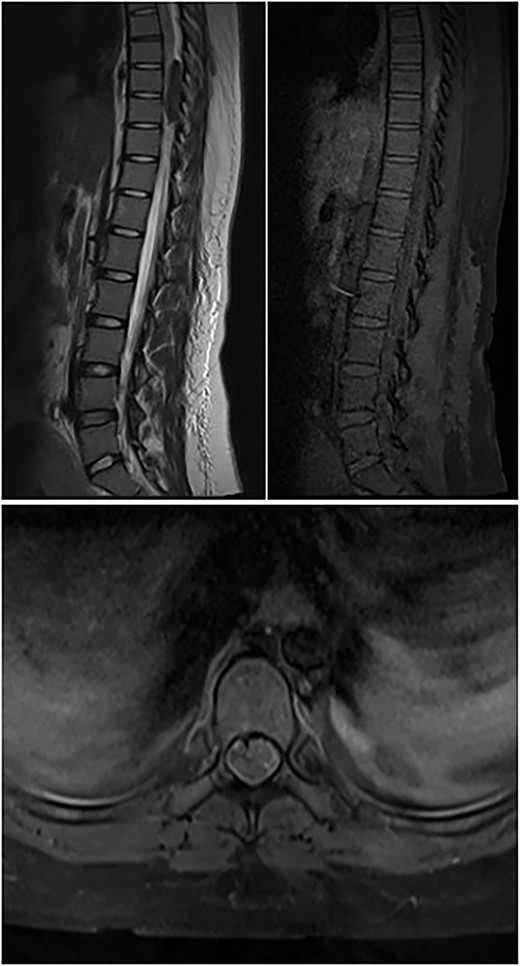

A 23-year-old female presented with acute onset paraparesis following an uneventful caesarean section under spinal anaesthesia. The patient presented to us 3 days after delivery and was paraplegic on examination with a sensory level of D10 and absent deep tendon reflexes in the lower limbs. MRI of the dorsal spine revealed oval well defined T1 hyperintense, T2 hypointense and heterogenous contrast enhancing extradural lesion on the dorsal epidural space at the D8–9 levels compressing the spinal cord and displacing it to the left. Resulting in long-segment cord signal change from D5 to 11 (Fig. 2). The lesion was 4.3 cm in its longitudinal extent and was hypointense on GRE suggestive of blood degradation products. A spinal DSA was performed but did not reveal any abnormality. The patient was operated the following day with D7–9 laminectomy via a posterior approach. Unfortunately, the patient had persistent deficit and continued to remain paraplegic despite extensive rehabilitation. A follow-up MRI scan at 3 months did not reveal any residual tumour.

Top left image shows preoperative T2W sagittal MRI of the dorsal spine showing hypointense lesion in the posterior epidural space at D8–9; top right image shows T1W pre-contrast fat-suppressed image showing hyperintensity; bottom image shows post-contrast T1W axial image showing minimal contrast enhancement.